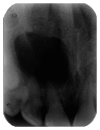

The aim of this case report is to present two cases where cone beam computed tomography (CBCT) was used for the diagnosis, treatment planning, and followup of large periapical lesions in relation to maxillary anterior teeth treated by endodontic surgery. Periapical disease may be detected sooner using CBCT, and their true size, extent, nature, and position can be assessed. It allows clinician to select the most relevant views of the area of interest resulting in improved detection of periapical lesions. CBCT scan may provide a better, more accurate, and faster method to differentially diagnose a solid (granuloma) from a fluid-filled lesion or cavity (cyst). In the present case report, endodontic treatment was performed for both the cases followed by endodontic surgery. Biopsy was done to establish the confirmatory histopathological diagnosis of the periapical lesions. Long-term assessment of the periapical healing following surgery was done in all the three dimensions using CBCT and was found to be more accurate than IOPA radiography. It was concluded that CBCT was a useful modality in making the diagnosis and treatment plan and assessing the outcome of endodontic surgery for large periapical lesions.